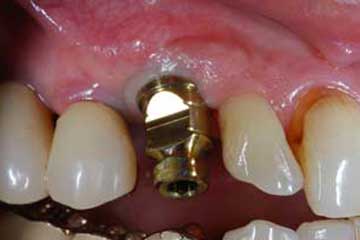

Con protesi fissa superiore e protesi fissa inferiore

I denti irrecuperabili dell'arcata superiore ed inferiore del paziente di anni 65

sono stati sostituiti da 10 impianti, cioè protesi radicolari endo-ossee che sostengono le protesi fisse superiore ed inferiore.